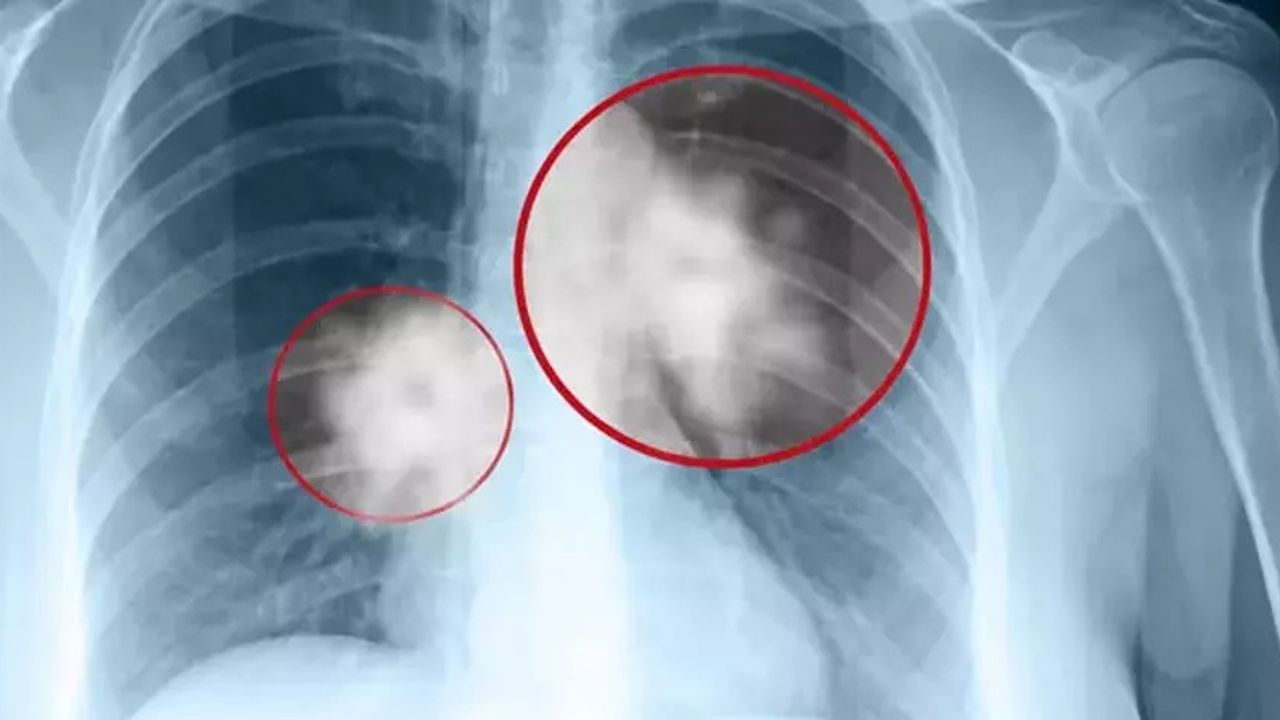

VM Medical Park Samsun Hastanesi Göğüs Cerrahisi Uzmanı Opr. Dr. Volkan Yılmaz, akciğer kanseri konusunda önemli uyarılarda bulundu. Dr. Yılmaz, akciğer kanserinin genellikle 50 yaş ve sonrasında görülmeye başladığını belirterek, sigara ve diğer risk faktörlerine sahip kişilerin şikayetleri olmasa dahi akciğer grafisi ve düşük doz tomografi ile tetkik yaptırmaları gerektiğini vurguladı.

Belirtiler ve Erken Tanı

Dr. Yılmaz, akciğer kanserinde erken teşhisin tedavi başarısını artırdığını belirterek, şu ifadeleri kullandı:

"Sıklıkla öksürük, nefes darlığı, hemoptizi (kanlı balgam) ve göğüs ağrısı gibi spesifik belirtilerle başvuran hastalarda; halsizlik, kilo kaybı ve ateş gibi non-spesifik şikayetler de görülebilmektedir."